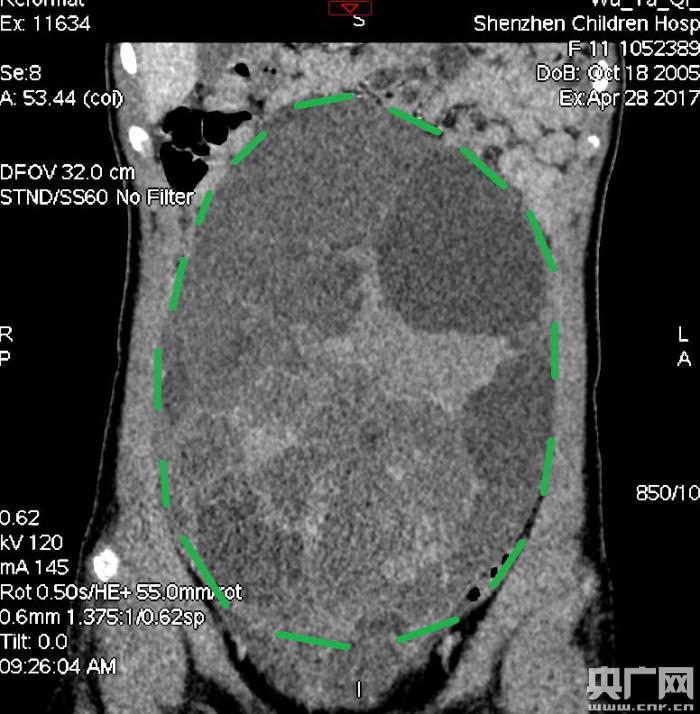

入院后,普外一科肖東主任向家長(zhǎng)詢問了病史,仔細(xì)進(jìn)行了體格檢查,并完善腹部CT。CT結(jié)果提示,孩子的大部分腹腔、盆腔被一個(gè)巨大的腫瘤占據(jù),腸道、血管和腎盂都受到了不同程度的壓迫。從CT上看,腫瘤很可能起源于左側(cè)的卵巢。

手術(shù)中發(fā)現(xiàn),小琪腹中的腫瘤體積巨大,大小約為25×20×15厘米,表面光滑,來源于左側(cè)卵巢。醫(yī)生們首先將其與周圍的組織小心剝離,然后將這個(gè)占據(jù)孩子腹腔、盆腔大部分的巨大包塊完整切除,切除腫瘤后還重建了左側(cè)卵巢。剖開瘤體,發(fā)現(xiàn)瘤體為囊性及實(shí)性混合組成,瘤體內(nèi)部充盈著粘液狀的液體,重量達(dá)到了3000克。術(shù)后小琪病情穩(wěn)定,測(cè)量腹圍從術(shù)前的72厘米減小到了62厘米。